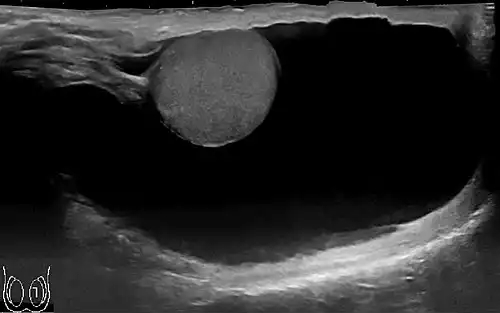

تشخیص بر اساس معاینه بالینی می باشد. در معاینه بیضه، بزرگی آن قابل مشاهده است و پزشک از پشت بیضه نور به پوست بیضه می تاباند که به آن ( TRANSILLUMINATION ) گویند. این معاینه به منظور بررسی وجود توده در بیضه ( سرطان بیضه ) صورت می گیرد. وقتی نور به پوست بیضه تابیده می شود، مایع اطراف بیضه روشن می شود و وجود توده در این حالت رد می گردد. اگر توده یا سرطان وجود داشته باشد، نور از مایع رد نمی شود و مایع روشن نمی شود. تشخیص قطعی با انجام سونوگرافی بیضه می باشد.